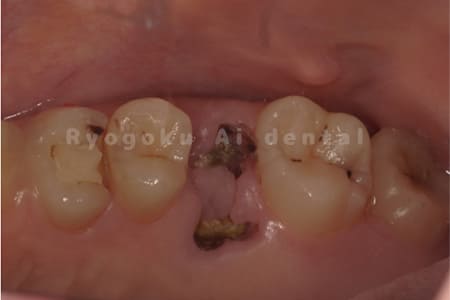

Case10

- 右下6番 重度カリエス

- 右下8を右下6へ移植に自家歯牙移植

- 治療期間

-

- 220,000円

右下の銀歯が外れかかっているとのことでご来院された患者様です。虫歯が大きく、かつ歯が割れており、保存不可能と判断し、親知らずの移植を行いました。

<リスク・副作用>

治療後、痛みや違和感、出血、腫れなどが出る事があります。喫煙者、糖尿病などの方の場合、歯が生着しない場合があります。